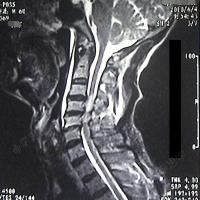

音频病例点评:椎管狭窄,脊髓水肿该怎么治疗?

提示脊髓出血伴水肿,病变范围累及全段颈髓和上段胸髓"考虑脊髓肿瘤"

原发性颈髓内生殖细胞瘤1例

延髓水肿,颈髓空洞形成,不知预后如何